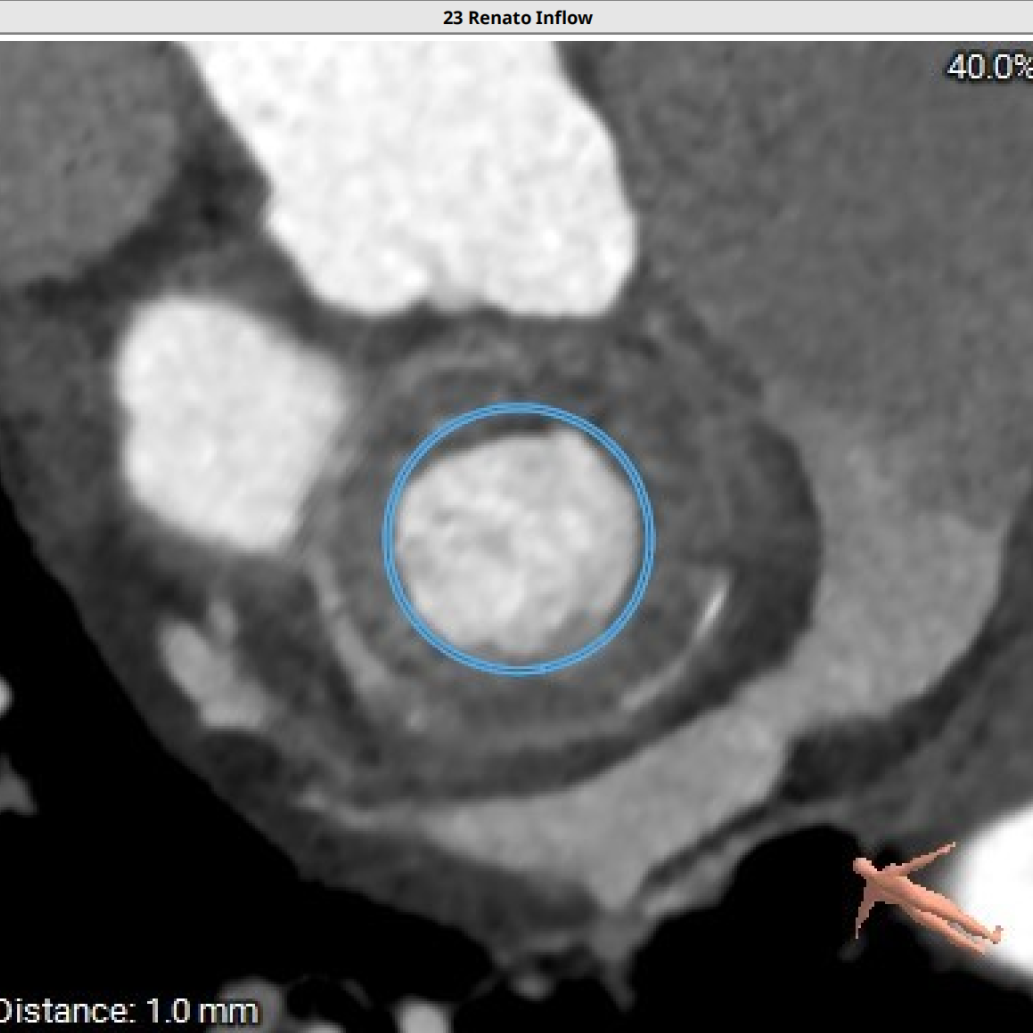

模拟23#Renatus植入